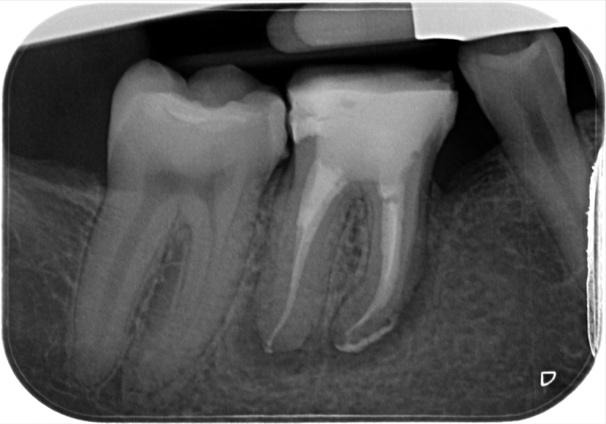

Immediate post-op and 18-month review IOPA

Displaying nice healing and a marked reduction in the PARL. RD sent review x-ray mentioning marginal gap at distal crown margin which ideally needs rectifying to maintain an optimal coronal seal on the root treatment!